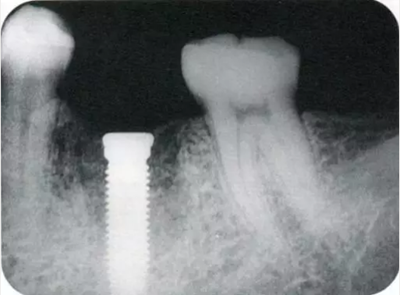

同時期的曲面斷層片。

種植體植入后的X光片